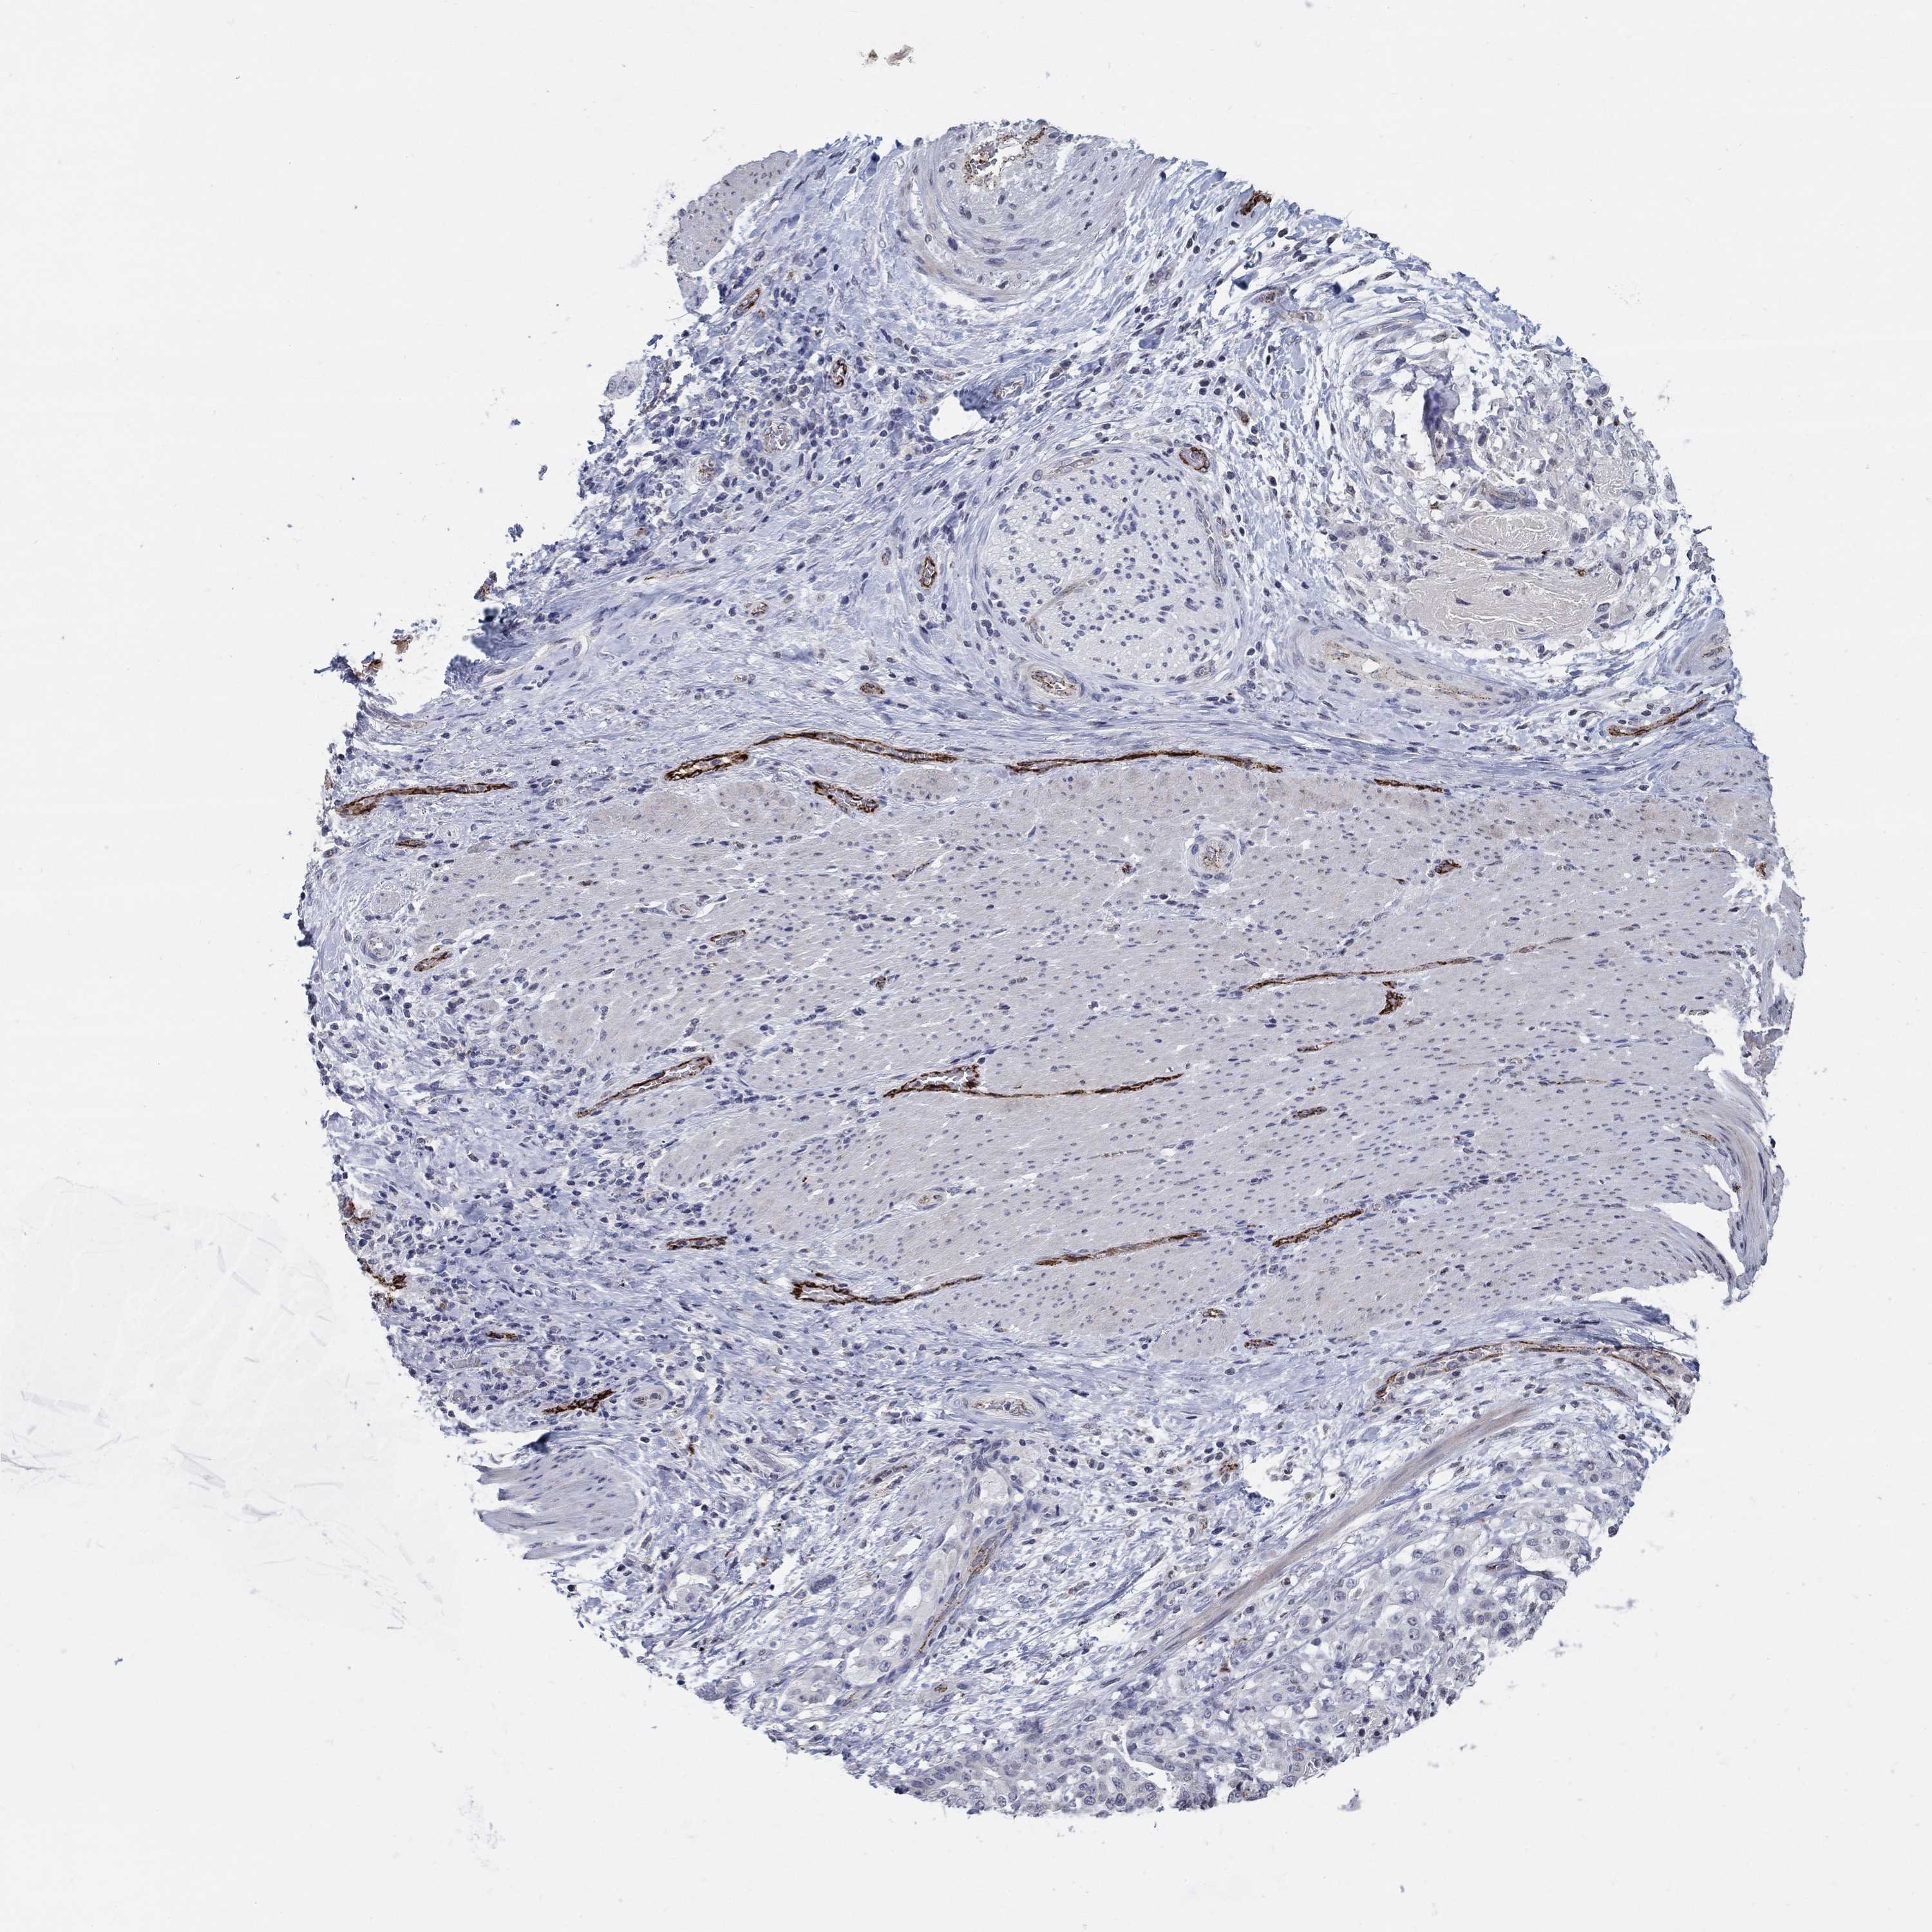

STOMACH CANCER - Protein expressioni

A mouse-over function shows sample information and annotation data. Click on an image to view it in a full screen mode. Samples can be filtered based on level of antibody staining by selecting one or several of the following categories: high, medium, low and not detected. The assay and annotation is described here.

Note that samples used for immunohistochemistry by the Human Protein Atlas do not correspond to samples in the TCGA dataset.

Antibody stainingi

Antibody staining in the annotated cell types in the current human tissue is reported as not detected, low, medium, or high, based on conventional immunohistochemistry profiling in selected tissues. This score is based on the combination of the staining intensity and fraction of stained cells.

Each image is clickable and will lead to virtual microscopy that enables deeper exploration of all samples and also displays staining intensity scores, fraction scores and subcellular localization as well as patient and tissue information for each sample.

Antibody HPA035427

Antibody HPA073753

Staining

High

Medium

Low

Not detected

Intensity

Strong

Moderate

Weak

Negative

Quantity

>75%

75%-25%

<25%

None

Location

Nuclear

Cytoplasmic/membranous

Cytoplasmic/membranous,nuclear

Adenocarcinoma, NOS

Adenocarcinoma, High grade